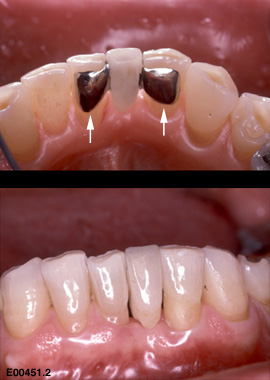

პროტეზირების ეს ტექნიკა პირველად მერილენდის უნივერსიტეტში შემუშავდა და მისი სახელწოდებაც აქედან მოდის. მას “ადჰეზიური ხიდის” სახელწოდებითაც მოიხსენიებენ. თავდაპირველად იგი წარმოადგენდა მეტალის კარკასზე დამაგრებულ ხელოვნურ კბილს. მეტალის “ფრთები” გვერდითი კბილების უკანა ზედაპირზე მაგრდებოდა ისე, რომ კბილის დამუშავება საჭირო არ იყო. რამდენადაც ასეთი მიმაგრება შედარებით სუსტია, მერილენდის ხიდი ფრონტალური კბილების აღსადგენად გამოიყენება (დროებით ან მუდმივად).

მეტალის კარკასის გამოყენებისას მერილენდის ხიდის ესთეტიკური მხარე არასახარბიელო იყო, მითუმეტეს რომ ეს ფაქტორი წინა კბილების ზონაში ყველაზე მნიშვნელოვანია. მეტალი ხელოვნურ კბილს ნაკლებად გამჭვირვალეს ხდიდა, ვიდრე ეს ბუნებრივი კბილებისთვისაა დამახასიათებელი.

სტომატოლოგიაში ახალი, თანამედროვე მასალების გაჩენასთან ერთად მერილენდის ხიდის დამზადების ტექნიკა ბევრად გაუმჯობესდა, ისევე როგორ მისი ვიზუალური მხარე. დღეს მისი დამზადება შესაძლებელია მთლიანად მაღალი ხარისხის კერამიკისგან ან ცირკონიუმის ოქსიდისაგან ლაბორატორიული გზით, ან მინაბოჭკოვანი მასალისგან პირდაპირ პირის ღრუში, იმის მიხედვით მუდმივი კონსტრუქცია მზადდება თუ დროებითი. მერილენდის ხიდი დროებით გამოიყენება, მაგალითად, ფრონტალური კბილის ადენტიის ან კბილის ნაადრევად დაკარგვის შემთხვევაში, სანამ იმპლანტაცია ჩატარება იქნება შესაძლებელია. ასევე, იმპლანტაციის შემდეგ შეხორცების პერიოდში ესთეტიკური მიზნით, სანამ იმპლანტზე მუდმივი კბილის გვირგვინის დამაგრება იქნება შესაძლებელი.